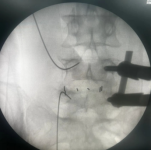

3.微创PKP技术:老年压缩性骨折球囊扩张椎体成形术

经皮球囊扩张椎体后凸成形术是皇冠娱乐城

很早就开展的一项微创技术,已经有20多年,每年手术约200例,尤其适用于老年骨质疏松引起的胸腰椎骨折;椎体转移性肿瘤(溶骨性破坏);引起疼痛症状的椎体血管瘤、多发性骨髓瘤、Kummell 症。局部麻醉,创伤小恢复快,第二天可以下床活动,迄今为止最高手术患者92岁高龄。